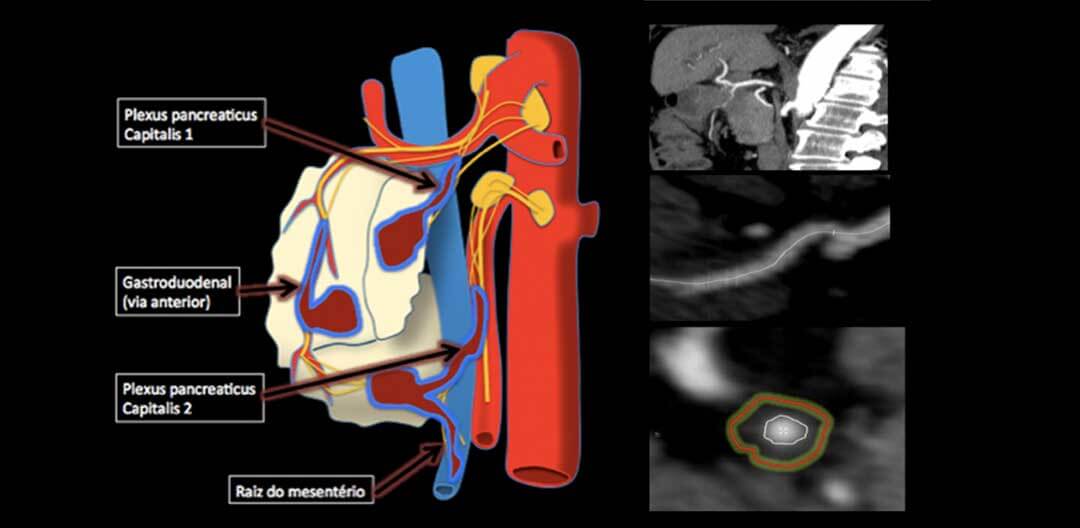

Qual o papel do radiologista na disseminação perineural no adenocarcinoma de pâncreas